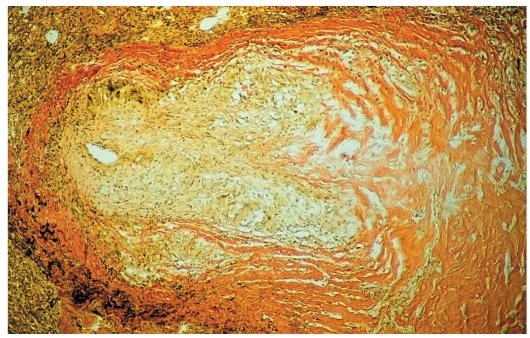

Карнификация Легкого: Микропрепараты и Диагностика

Раздел: Калейдоскоп образов